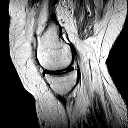

I called him the day I arrived here from Amsterdam to make an appointment for the knee operation as I had already sent him by email my scanned results of my MRI SCAN I had done last week in Amsterdam